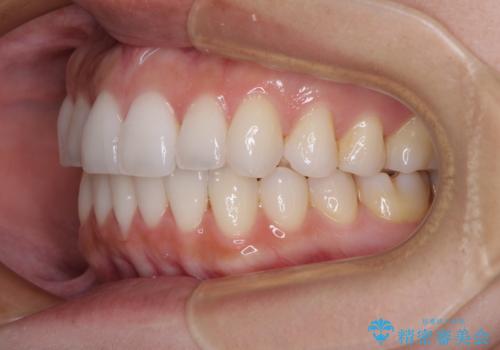

前歯のクロスバイト インビザラインによる矯正治療

- 上下のクロスバイトと前歯のデコボコを気にして来院された患者様です。

インビザラインを用い、IPR(歯と歯の間を削る)と歯列全体を拡大させることで、歯並びを整えていくこととしました。

治療を急いでいらっしゃらなかったため、のんびりと治療を進めていきました。3年以上の期間を要しましたが、きれいな口元に仕上がりました。